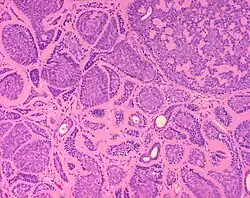

Micrograph of a dermal cylindroma in H&E stain.

Dermal cylindromas are:

- Dermal lesions consisting of nests of cells that are surrounded by hyaline (i.e., glassy, eosinophilic, acellular) material and have:

- Hyperchromatic nuclei that may palisade (columnar nuclei arranged around the periphery of the cell nests with their short axis tangential to the nest periphery), and

- Cells with lighter staining ovoid nuclei at their centre.

They lack of a significant number of lymphocytes; this differentiates them from spiradenomas.